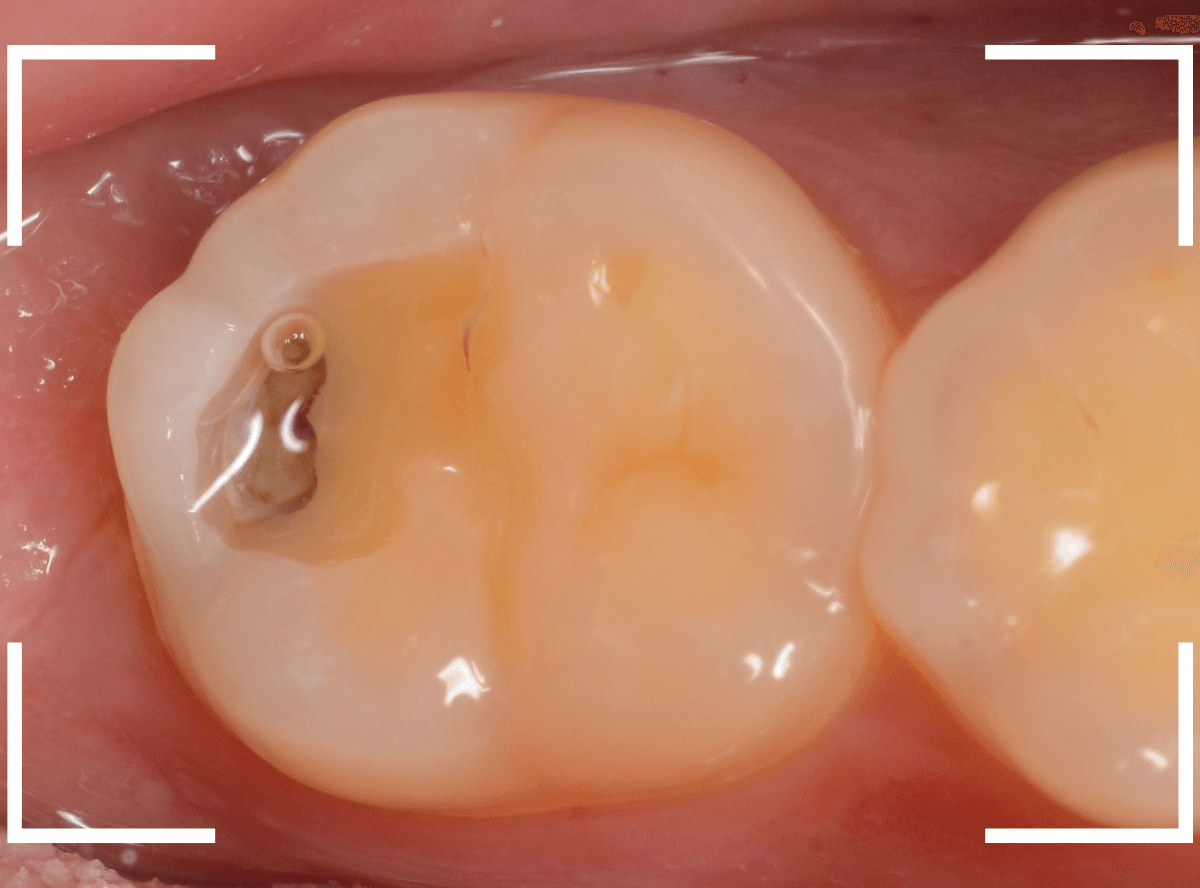

金属を外したところです。

写真では写ってしませんが、この奥に虫歯があります。

全ての虫歯を除去したところです。

抜歯した後ろのおやしらずは、元々虫歯の治療がしてありましたが、その際に抜歯しておいた方が良かったのではないかな、と思いました。